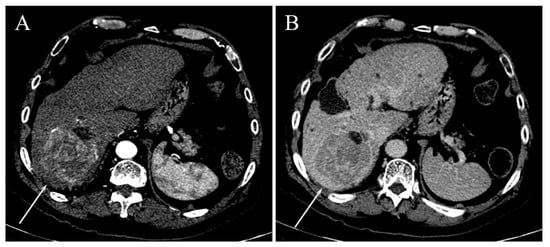

| Irregular margins | 21 (58.3%) | 26 (47.3%) | 0.391 |

| TTPVI | 14 (38.9%) | 11 (20%) | 0.058 |

| Peritumoral enhancement | 4 (11.1%) | 6 (10.9%) | 1.000 |